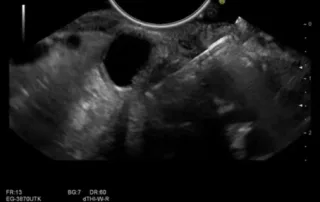

Ενδοσκοπικός υπέρηχος με σκιαγραφικό για την αξιολόγηση βλαβών του παγκρέατος

Η χρήση σκιαγραφικού κατά την διάρκεια του ενδοσκοπικού υπερήχου [...]